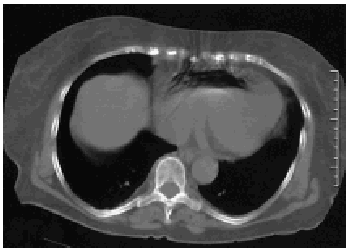

Se consultó a la UCI, donde se planteó la extracción del aire a través de un catéter central. Previamente, se realizó una nueva TC torácica de control, aproximadamente una hora después de la inyección, donde ya no se observa la burbuja aérea (fig. 2). Ante la falta de sintomatología secundaria a embolia aérea, se decidió mantener una actitud conservadora. La paciente fue dada de alta del hospital sin secuelas.

Figura 2.